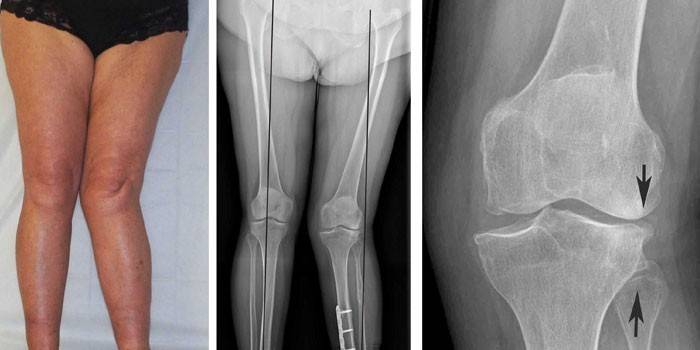

Hlavnými metódami diagnostiky artrózy sú identifikácia charakteristických klinických príznakov počas vyšetrenia a štúdia rádiografických snímok. Natáčanie chorého kĺbu sa vykonáva v dvoch projekciách, po ktorých odborník vyšetrí rádiologický obraz. Pre druhý stupeň choroby sú charakteristické tieto príznaky:

- deformácia a vyrovnanie miesta kosti;

- zúženie spoločného priestoru;

- kostné cystické formácie;

- osteofyty.